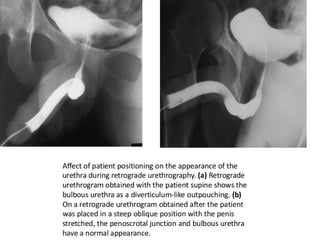

The document discusses retrograde urethrography (RGU) and its associated risks, including the potential for mucosal edema and complications from injecting contrast fluid. It highlights the importance of antibiotic cover in certain cases and the efficacy of cystography for diagnosing pelvic fractures, particularly in patients with hematuria. Additionally, it notes the incidence of urinary tract infections and reactions to contrast mediums in patients undergoing these procedures.